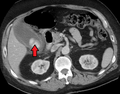

![]() Acute cholecystitis as seen on CT. Note the fat stranding around the enlarged gallbladder. | |

Right upper quadrant abdominal ultrasound is most commonly used to diagnose cholecystitis.[1][22][23] Ultrasound findings suggestive of acute cholecystitis include gallstones, fluid surrounding the gallbladder, gallbladder wall thickening, dilation of the bile duct, and sonographic Murphy's sign.[2] Given its higher sensitivity, hepatic iminodiacetic acid (HIDA) scan can be used if ultrasound is not diagnostic.[2][13] CT scan may also be used if complications such as perforation or gangrene are suspected.[13]

Acute cholecystitis with gallbladder wall thickening, a large gallstone, and a large gallbladder